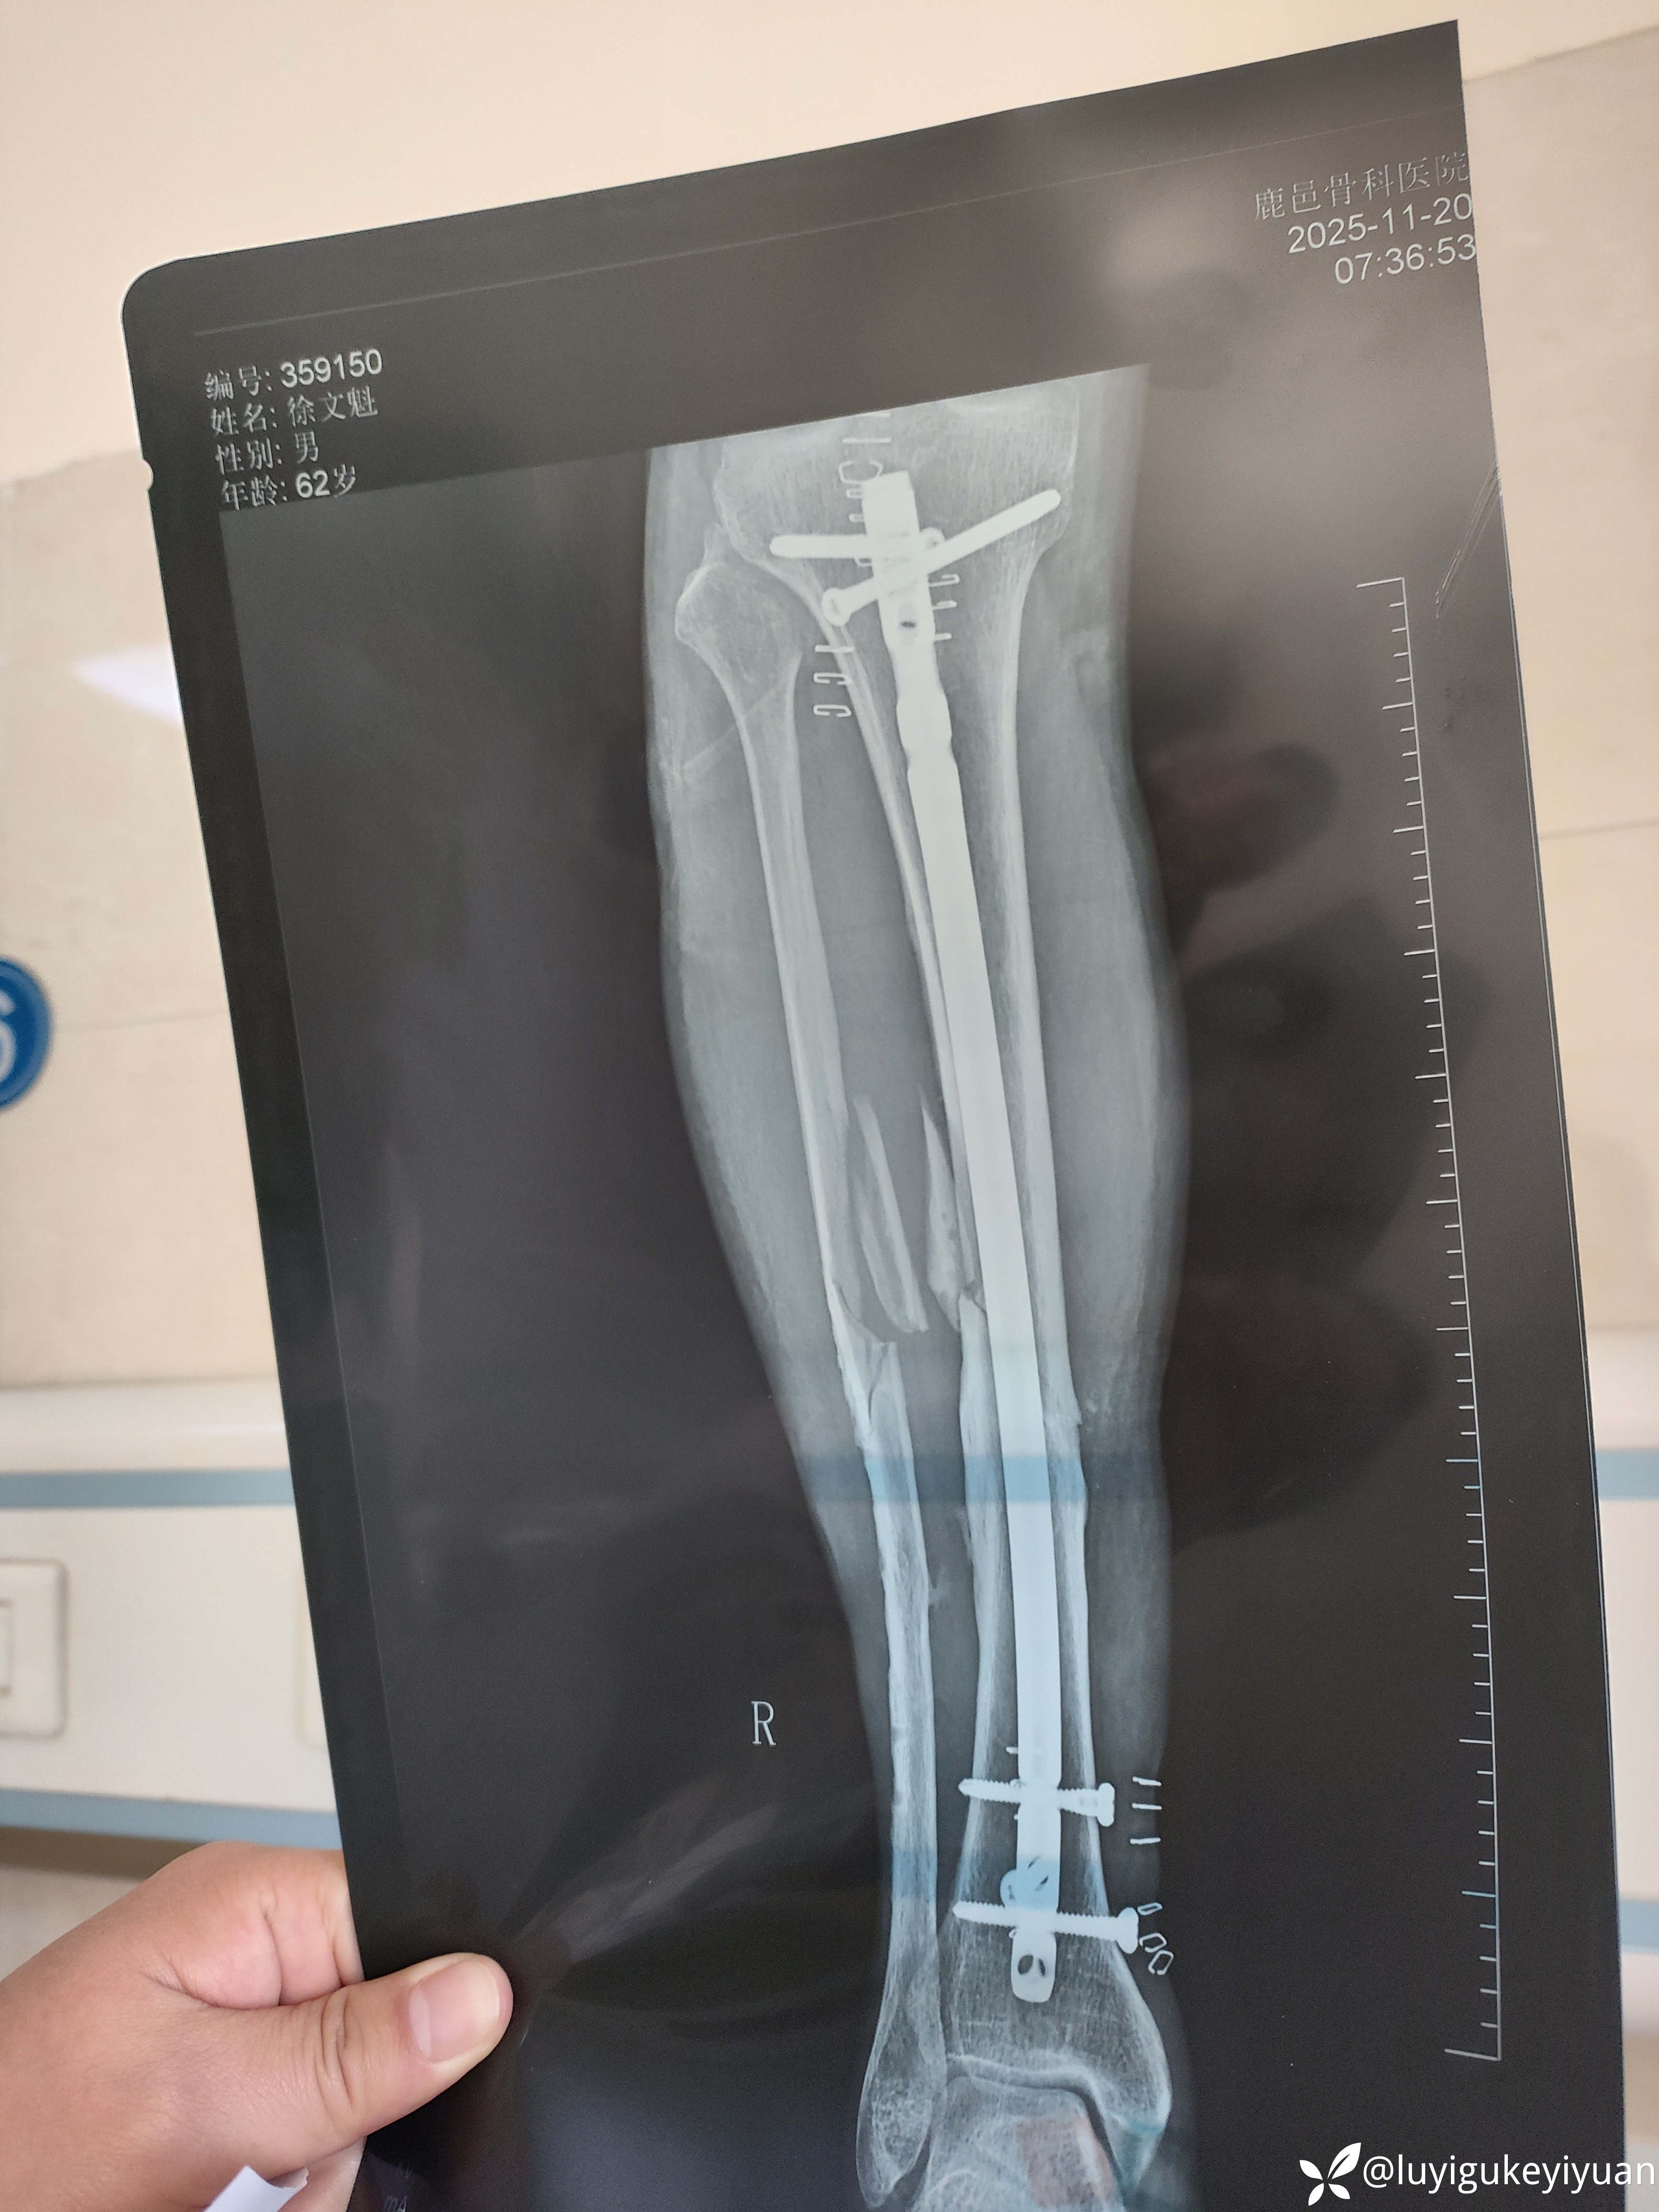

病例胫腓骨二次骨折

医患关系太紧张啊,术前谈话说的好好的,术后骨折部位不一定解剖复位,术后患者家属说手术不成功,真

无语!